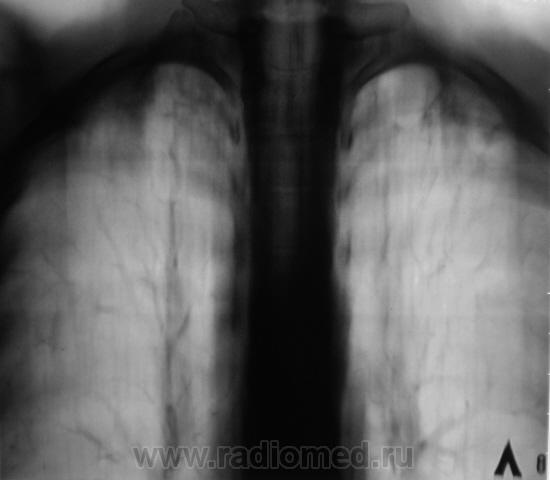

В 2009 году взяли пациента на контроль стандартно дообследовали.

Картинка была типичной, отправили на консультацию к фтизиатру, сделали все необходимые "отметки" в журналах и компе и успокоились, по поводу пациента.

Оказалось, что была сделана интересная запись - "Данных за активный туб. процесс не выявлено", объяснили, что МБТ в мокроте не были обнаружены, а что там было в баночке, возможно, половино "слюны", так то неизвестно...

Иногда, возникает в таких случаях справедливое "ожесточение" на коллег фтизиатров, решили сделать только срез "8".

Сравнили две "8" за 2009 и 2010 годы, и вновь, направили пациента на консультацию к фтизиатру.